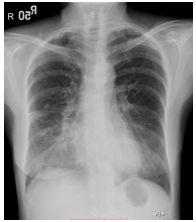

31.咳嗽 3 週